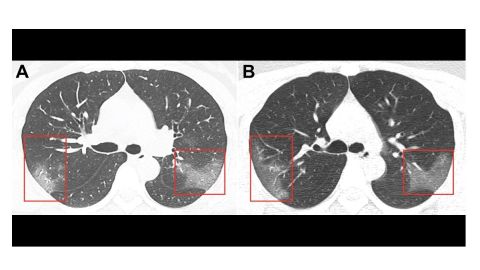

Así lucen los pulmones de una paciente de coronavirus. Crédito: Radiology | Cortesía

Su tomografía computarizada reveló unos parches que se ven como vidrio esmerilado, o líquido en los espacios en los pulmones. Estos son indicios que se encuentran comúnmente en las radiografías de pacientes con casos graves.

Normalmente, a una persona no se le realizaría una exploración del tórax, como en el escenario, pero los médicos hicieron una excepción en su caso. Encontraron opacidad de vidrio esmerilado en sus pulmones, las marcas de la neumonía Covid-19.